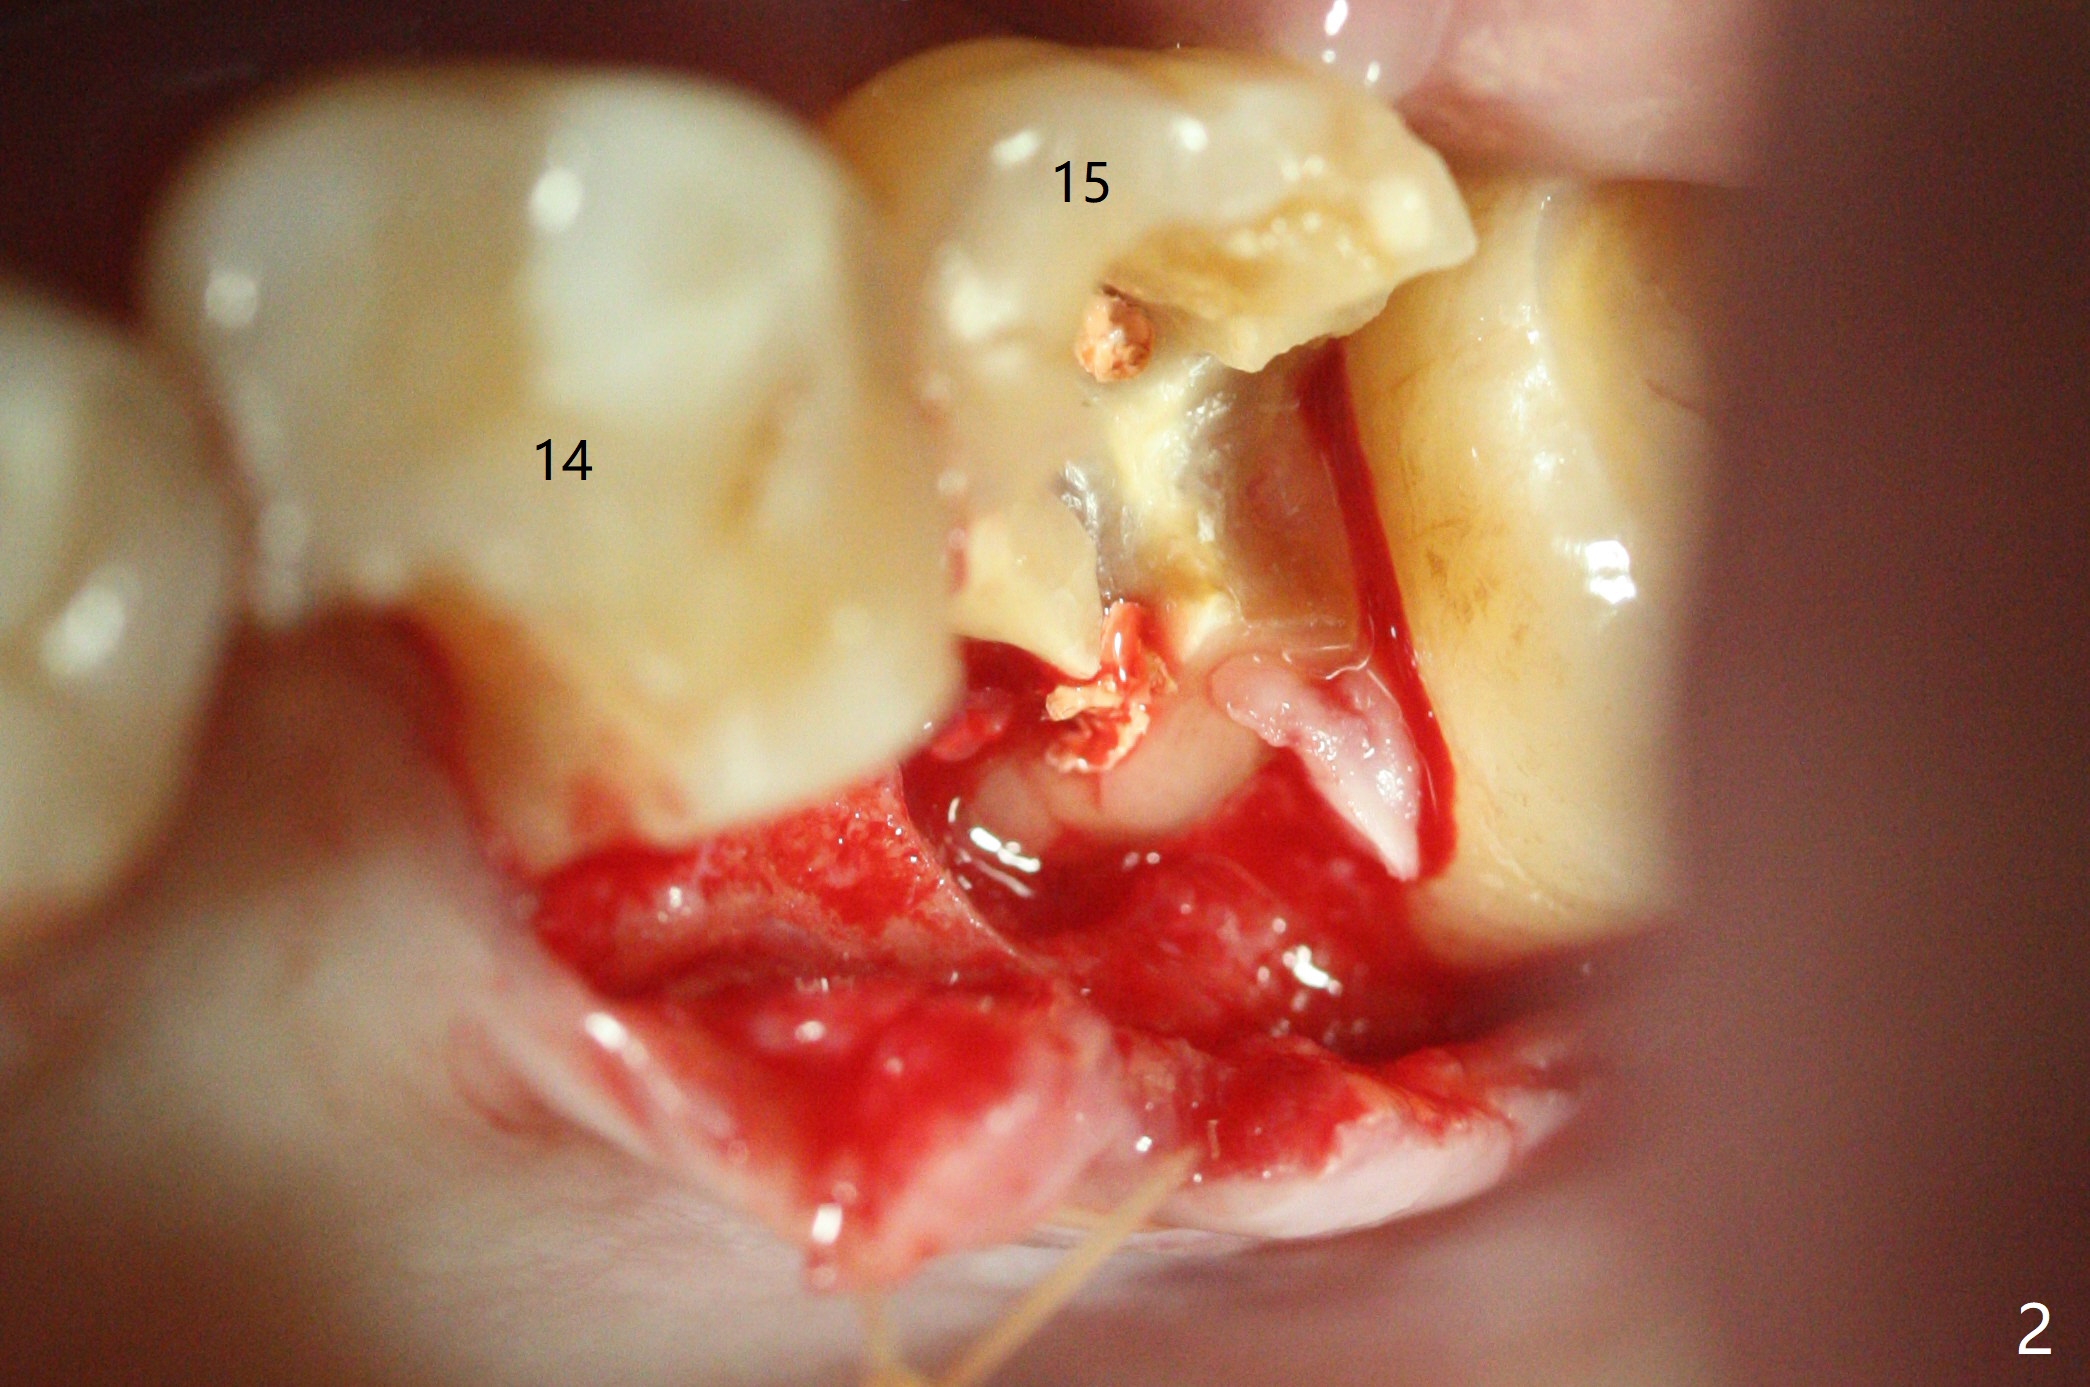

A 47-year-old man has pain at #2 and 15, while #14 has mesiolingual subgingival fracture (Fig.1). #2 is deemed non-salvageable by an endodontist, whereas RCT is finished at #15. When the patient returns for restoration, he reports that the filling is out at #15. In fact it has subcrestal fracture (Fig.2), while #14 equicrestal and difficult to restore (Fig.3). Although the patient agrees to have implants at #2 and 15, DB bone loss at #2 makes it difficult for implant (Fig.4). Use FC implant for primary stability. Insert a small piece of cotton pellet or healing screw and pack sticky bone around the implant before placing a temporary abutment. The latter will form a large gingival cuff, which makes it easy to place pair abutment without interference from the crestal bone. Screw loosening will be reduced. In fact there is PARL of the palatal root of #14 (Fig.5). A FC implant will be also placed at #15 for the same reason (Fig.6).